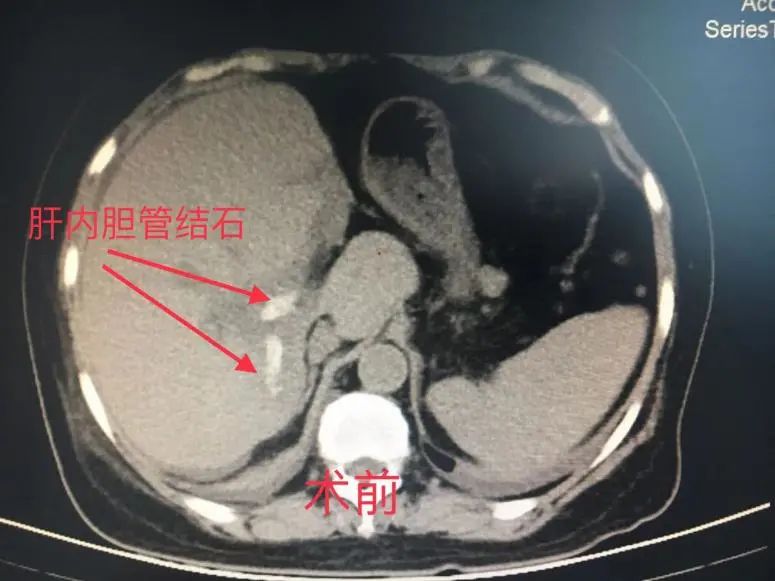

终于患者急性胆管炎再次发作,忍无可忍,经人介绍,患者来到了肝胆外科李金海副主任医师门诊,第一次见到患者看到的是一个极其虚弱的身体:全身皮肤及眼睛发黄,而且发热高达39℃,中上腹痛明显,术前胆红素指标更是高达134umol/L(正常值是0-28umol/L),提示右肝管脱落的结石已经引发胆总管梗阻,引起胆总管的急性梗阻性化脓性炎症。CT看起来患者的右后叶胆管已经有明显的“铸型结石”,按外科的原则,是需要手术治疗的。一双儿女听说母亲的病情,也从外地专门回到瑞安。患者女儿反复说我妈妈这个右肝管结石在北京协和医院手术的专家看了说是没办法祛除的。从患者本人紧锁的眉头看得出来,她对自己的疾病好像也并没有太大信心能治好。